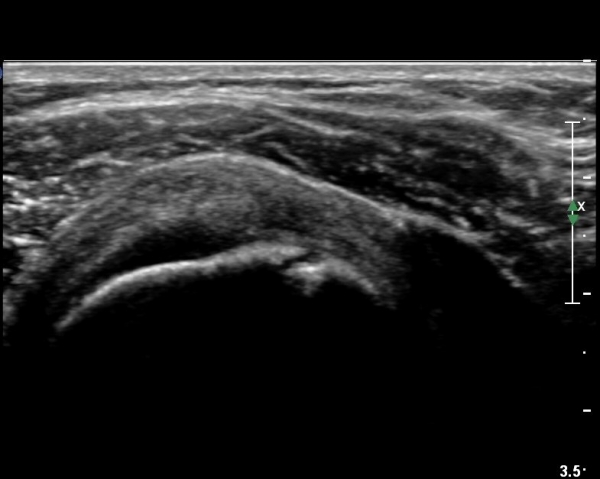

ÃÊÀ½ÆÄ °Ë»ç

´ë°áÀý°ú °ßºÀÇϺο¡ ¹æ»ç¼± Åõ°ú¼º °¨¼Ò(sclerosis)°¡ °üÂûµÈ´Ù(÷ºÎÆÄÀÏ).